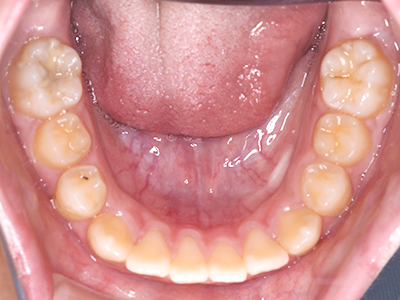

小児矯正について

歯並びの相談に来られるお子様は、口呼吸をしているケースが多く、これが歯並びに大きな影響を与えています。

ないき歯科クリニックでは、上あごの成長不足を補い、鼻呼吸を獲得しつつ歯列を整え、将来のお口をより健康な状態にすることをゴールに定める矯正治療をおこなっています。